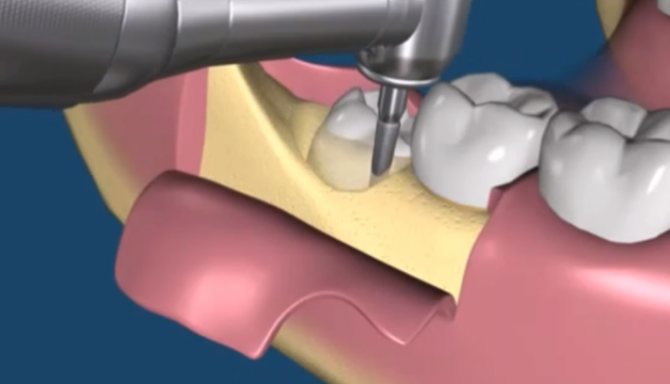

Удаление зубов – полноценное хирургическое вмешательство. Операция состоит из четырех этапов.

- Извлечения зуба после того, как анестезия заработала (десна немеет, сосуды сужаются). Для отсечения связок, фиксирующих зуб, пользуются скальпелем. Выбор инструментов и продолжительность процедуры зависят от состояния зуба.

Как проводится эта методика – если лунка пустая, то под анестезией костные стенки лунки выскабливаются кюретажной ложкой, чтобы создать кровотечение и лунка заполнилась кровью (видео 3). Если же лунка заполнена грануляциями, то их тщательно выскабливают, т.е. делают тот же кюретаж (видео 4). Далее в обоих случаях после того как лунка заполняется кровью – в глубь лунки кладется противовоспалительное лекарство (Альвожель), а на слизистую накладывается несколько швов, чтобы сблизить края раны. Сразу же назначаются антибиотики.